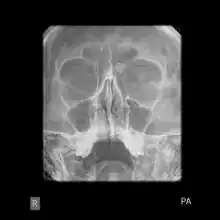

X-ray skull: Osteoma of the frontal sinus

Medical imaging such as X-ray, CT scan and MRI show dense, clearly defined, round white tumors attached to bone.[1] They may be diagnosed when having medical imaging for another reason.[3] Osteomas of the paranasal sinuses and skull base can be diagnosed using CT-scan without intravenous contrast, allowing its size and relation to nearby important structures to be assessed.[3] A biopsy is not usually required.[3]